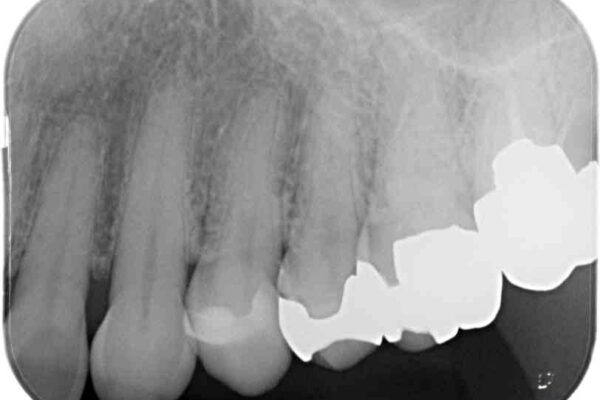

治療後

• 外れてしまった銀歯 セラミックインレーで自然な仕上がりに 治療後画像

正面から見える場所であったため、セラミックインレーで自然な口元にすることができました。